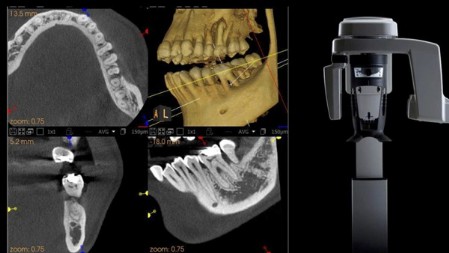

TC Cone Beam 3D (CBCT)

Con il termine TC Cone Beam (CBCT), si intende una macchina capace di scansionare le arcate dentali del paziente attraverso l’emissione di una dose molto bassa di raggi X fornendo immagini tridimensionali di altissima qualità delle ossa mascellari e dei denti. La tomografia Computerizzata Cone Beam 3D rappresenta pertanto il massimo raggiungibile nel campo della radiodiagnostica odontoiatrica.

Come si effettua l’esame?

- La Cone Beam è un esame assai semplice e veloce ma, soprattutto, indolore.

Il paziente viene fatto avvicinare ad un’apparecchiatura molto simile al classico ortopanoramico (quindi aperta e non chiusa come le classiche T.A.C.) e si provvede a sistemare la testa del paziente in modo che il mento appoggi su braccio appositamente regolabile e la testa venga mantenuta in posizione da due asticelle, anch’esse regolabili.La parte superiore della macchina girerà attorno alla testa del soggetto allo scopo di raccogliere le informazioni riguardo al cavo orale in esame che poi verranno organizzate dal software il quale fornirà la rappresentazione tridimensionale delle ossa, dei denti, e del parodonto.La durata complessiva dell’esame è di pochi secondi. E’ possibile stabilire se scansionare una sola arcata oppure entrambe in una sola volta, oppure una zona settoriale specifica.